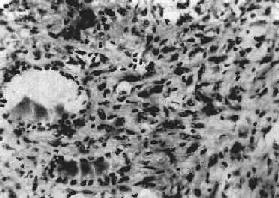

五、甲状腺肿瘤(一)甲状腺腺瘤 甲状腺腺瘤(thyroid adenoma)是常见的甲状腺良性肿瘤,多见于青、中年妇女,出现功能亢进者不过1%。肿瘤绝大多数为单发,大小从直径数毫米到3~5cm。肿瘤中心有时可见囊性变、纤维化或钙化。借助以下特点可与结节性胶样甲状腺肿中的结节相区别:有完整的包膜,压迫周围组织,瘤内组织结构比较一致,其形态与周围甲状腺组织不同。病理组织学上可分为以下两种。 1.滤泡性腺瘤(follicular adenoma)根据滤泡分化程度,又可分为以下几种亚型:①胚胎性腺瘤(embryonal adenoma),瘤细胞小,排列成条索状或小片状,有少量不完整的滤泡状腺腔散在,有较多呈水肿的疏松纤维间质;②胎儿型腺瘤(fetal adenoma),由许多小滤泡构成,上皮细胞为小立方形,滤泡腔内多不含胶质,与胎儿甲状腺组织相似(图15-9)。间质较丰富,呈水肿或粘液变性,此型易发生囊性变或出血;③单纯型腺瘤(simple adenoma),由与正常甲状腺相似的滤泡构成,间质较少;④胶样腺瘤(colloid adenoma),滤泡较大,充满胶质,间质少;⑤嗜酸性细胞腺瘤(acidophilic cell adenoma,亦称Hürthle cell adenoma),瘤细胞大而多角形,核小,胞浆丰富,有嗜酸性颗粒,排列成索状或巢状,也可形成不完整的滤泡腔。本瘤较少见。

图15-9 胎儿型甲状腺腺瘤 2.乳头状腺瘤(papillary adenoma)滤泡上皮细胞排列成单层,呈乳头状向腺腔内突出,滤泡常形成大囊腔,故亦称囊性乳头状瘤。间质少,肿瘤常并发出血、坏死及纤维化。 (二)甲状腺癌 甲状腺癌(carcinoma of thyroid)在不同地区发病率差别很大,虽然本病恶性程度不同,与其他器官癌相比,发展较缓慢。值得注意的是,有的原发灶很小,临床上常首先发现转移病灶。主要有以下4种类型。 1.乳头状腺癌(papillary adenocarcinoma)占甲状腺癌的40%~60%,青少年女性多见,生长较慢,肉眼发现时多为1~2cm的圆形肿块,无包膜,少数有不完整的包膜,以后逐渐向周围浸润。切面灰色或灰棕色,质地有的较软有的软硬。镜下,癌细胞围绕一纤维血管中心轴呈乳头状排列,乳头分支较多(图15-10)。癌细胞立方形或矮柱状,其特点是核染色质少,呈透明或毛玻璃样,无核仁。可伴有单纯型甲状腺滤泡,间质中常有砂粒体出现。本癌发现时约50%已有颈部淋巴结转移,有时原发灶后于转移灶发现,有的原发灶甚至小到难以觉察的程度。此癌恶性程度低,5年存活率达75%。